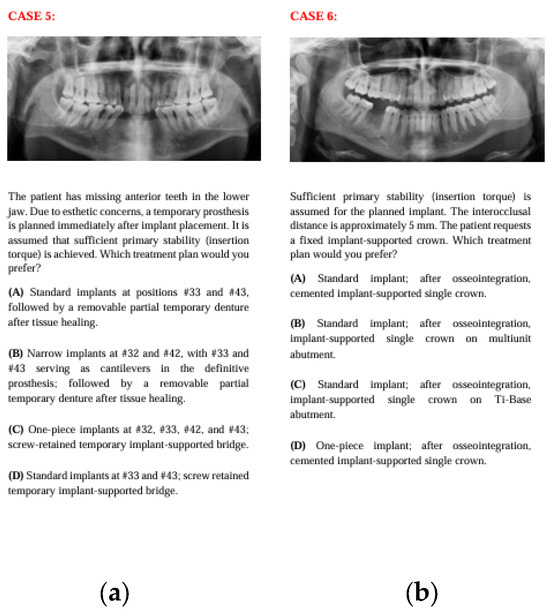

Figure 3. The panoramic radiographs, descriptions, and four treatment options of Case 5 (a) and Case 6 (b).